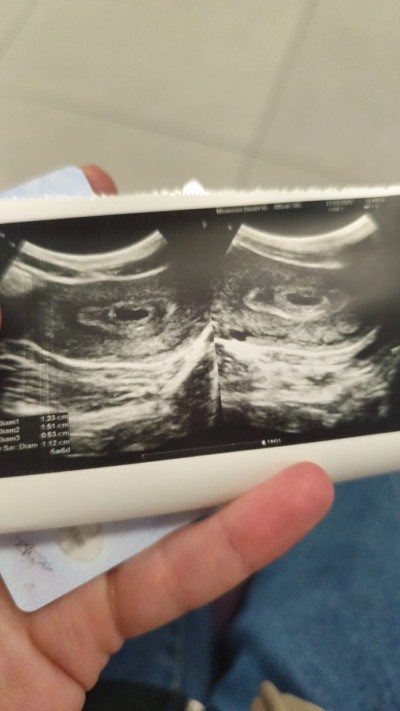

kizlar kese var Bebek yok 6+0 normalmi tekrar kontrole ne zaman gitmeliyim

Gebelik haftası 6

Bu görüntüde kesede bebek var görünüyor canım. Doktor yok dediyse hemen doktorunu değiştir. Çünkü şu sıralar erken haftalarda hep bebek yok deyip kürtaja yönlendiriyor doktorlar anlamış değilim. Buna bir denetleme gelmesi lazım. 28 haftalığım, şu uygulamada en çok gördüğüm şikayet bu. Kese var bebek yok. Haftan kaç? Ya 6 ya 7. Ben bebeği de kalp atışını da 8. Haftada gördüm ve duydum. Onu da vajinal muayene ile zar zor. Karından 10-11. Haftada bile net görünmüyordu bebek. Sakın telaşa kapılıp boş gebelik diye kendini perişan etme.

Parmağının üstündeki yani sağ taraftaki fotoğrafta kesenin solunda küçük bir beyaz leke görünüyor. O bebeğin eşi dediğimiz parçanın görüntüsü gibi duruyor. Yolk sac denilen şey yani. O varsa çok yüksek oranda bebek de oluşuyor. Bir ya da biraz daha sabredersen iki hafta sonra bebeği görüp kalp atışını duyabilirsin bence. Uzman değilim ama görüntü çok belirgin. Sağlıklı beslenmeye ve dinlenmeye gayret et. Sağlıkla gelsin bebeğin.

Saç diam ne demek oluor bilgin varmi

Kese boyutu ölçüleri sanırım. Onlara çok takılma. İlk haftalarda ölçümler doğru olmuyor genelde. Çok küçük olduğu için cihazlar ölçüm yapamıyor. Doktorlar da görüntüyü yakınlaştırıp tahmini noktalar belirleyerek ölçüm yapıyorlar. İlerleyen haftalarda daha iyi farkedersin. Bir kontrolde ilerden gidiyor derler diğer kontrolde geriden geliyor derler. +- iki haftaya kadar da normal kabul ediliyor.